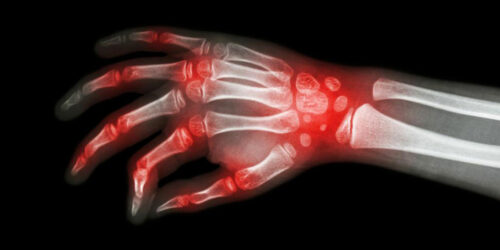

Lupus and rheumatoid arthritis are both autoimmune conditions that are often confused to be the same. The fact that these – rheumatoid arthritis, lupus are autoimmune diseases makes their symptoms similar too. Auto immune diseases are typically those conditions where the immune system of the body attacks healthy cells, causing inflammation, swelling, and pain in the affected areas.